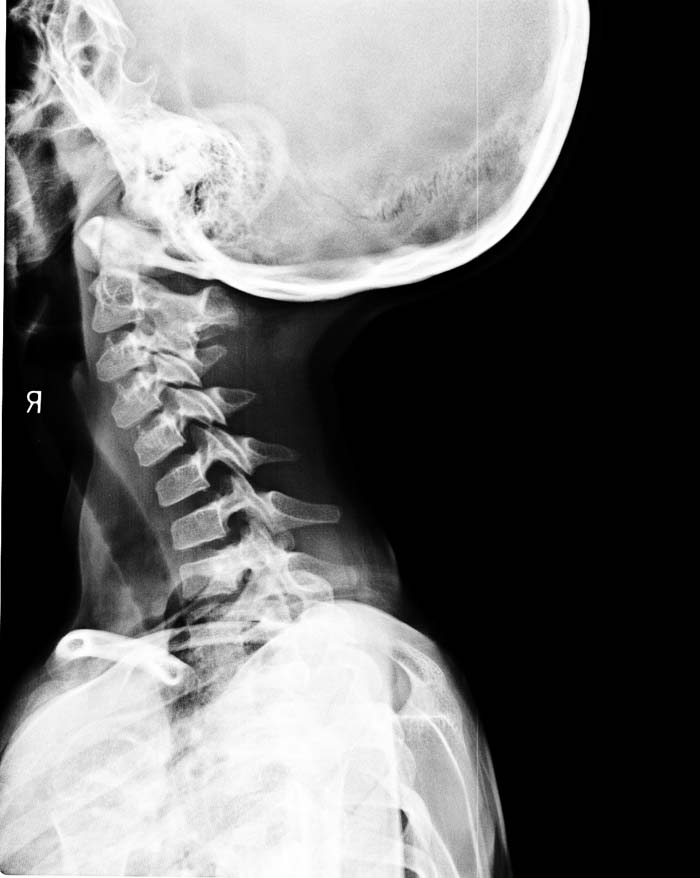

以下是引用zsl6918在2009-10-17 18:51:00的发言:[br]融椎畸形

以下是引用zy_zj在2009-10-17 19:21:00的发言:[br]胸椎8,9椎体融合畸形,伴序列s形弯曲,颈椎稍侧弯,曲度反向。

以下是引用余辉在2009-10-18 10:20:00的发言:[br]支持椎体隔合畸形,肋骨亦有融合,局部椎体密度较低,棘突影像缺如,不排除合并椎体裂,建议ct检查